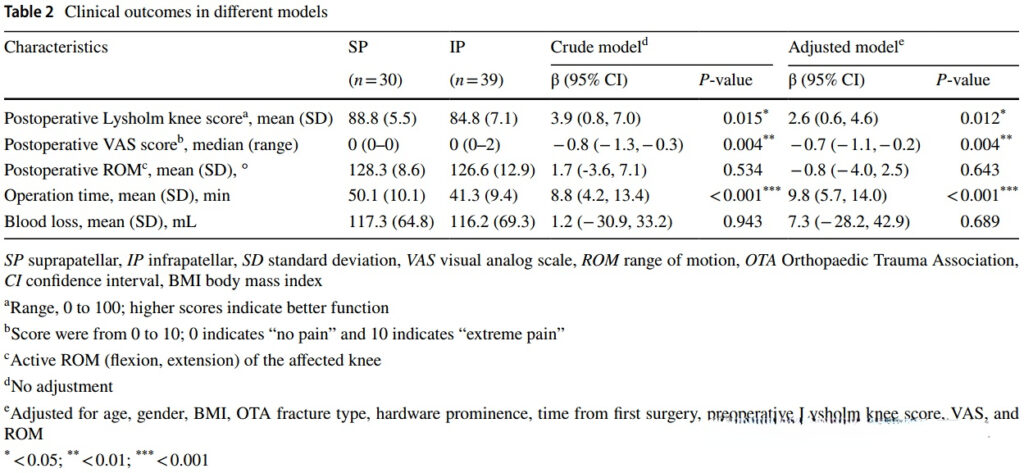

In this study, the authors included 69 patients, of whom 30 were removed suprapatellar and 39 were removed infrapatellar. The suprapatellar group had a higher Lysholm score and a lower VAS score.